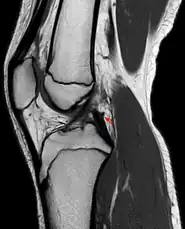

The Posterior meniscofemoral ligament (also known as the ligament of Wrisberg) is a small fibrous band of the knee joint. It attaches to the posterior area of the lateral meniscus and crosses superiorly and medially behind the posterior cruciate ligament to attach to the medial condyle of the femur.[1]

The posterior meniscofemoral ligament is found in 64.4% of the subjects in MRI scan of the knee.[1]